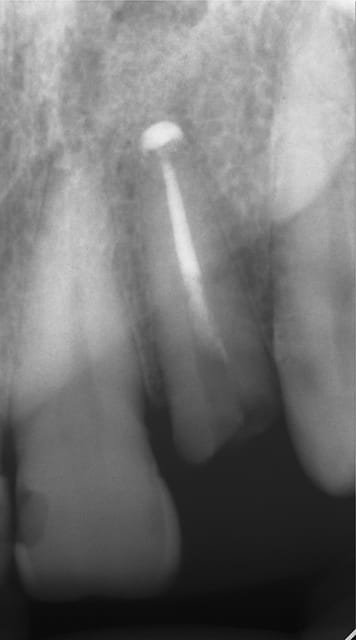

Photos d'un cas d'extraction implantation immédiate, stabilité primaire (de mémoire) assez élevée.. 60/70 N ..démontage du gingiva clips et du shuttle, pilier serré 40N, couronne procera

Merci pour le cas, bien fait. Belle présentation photo.

Assez classique d'un implant 2 pièces.

Le contour gingival est net, belle guérison, c'est à combien de semaine ?

Je vois un peu de ciment sur la radio finale, attention, c'est pas bien pour les tissus.

Oui je sais pour le ciment... j'utilise d'ailleur ce cas et cette radio dans une présentation pour mettre en garde sur le risque au moment du scellement de voir du ciment fuser sous la limite prothétique vers la col de l'implant..galère à éliminer...Personnellement je préfere plutot utiliser des piliers à usiner (maintenant disponibles voir shop online pour photos) au lieu des strandarts meme si il y a deux hauteurs/col implantaire en 1 et 3mm aujourd,hui disponibles..A l'époque de ce cas il n'y avait que les 1 mm et la limite est un "poil" trop profonde.

La pose de la couron nec'est faite 8 semaines apres l'extraction implantation immédiate, la particularité de ce systeme permet de ne pas démonter le shuttle ni la gingivaclip pour l'empreinte..je pense que ca aide bien à la qualité gingivale...radio controle ci jointe